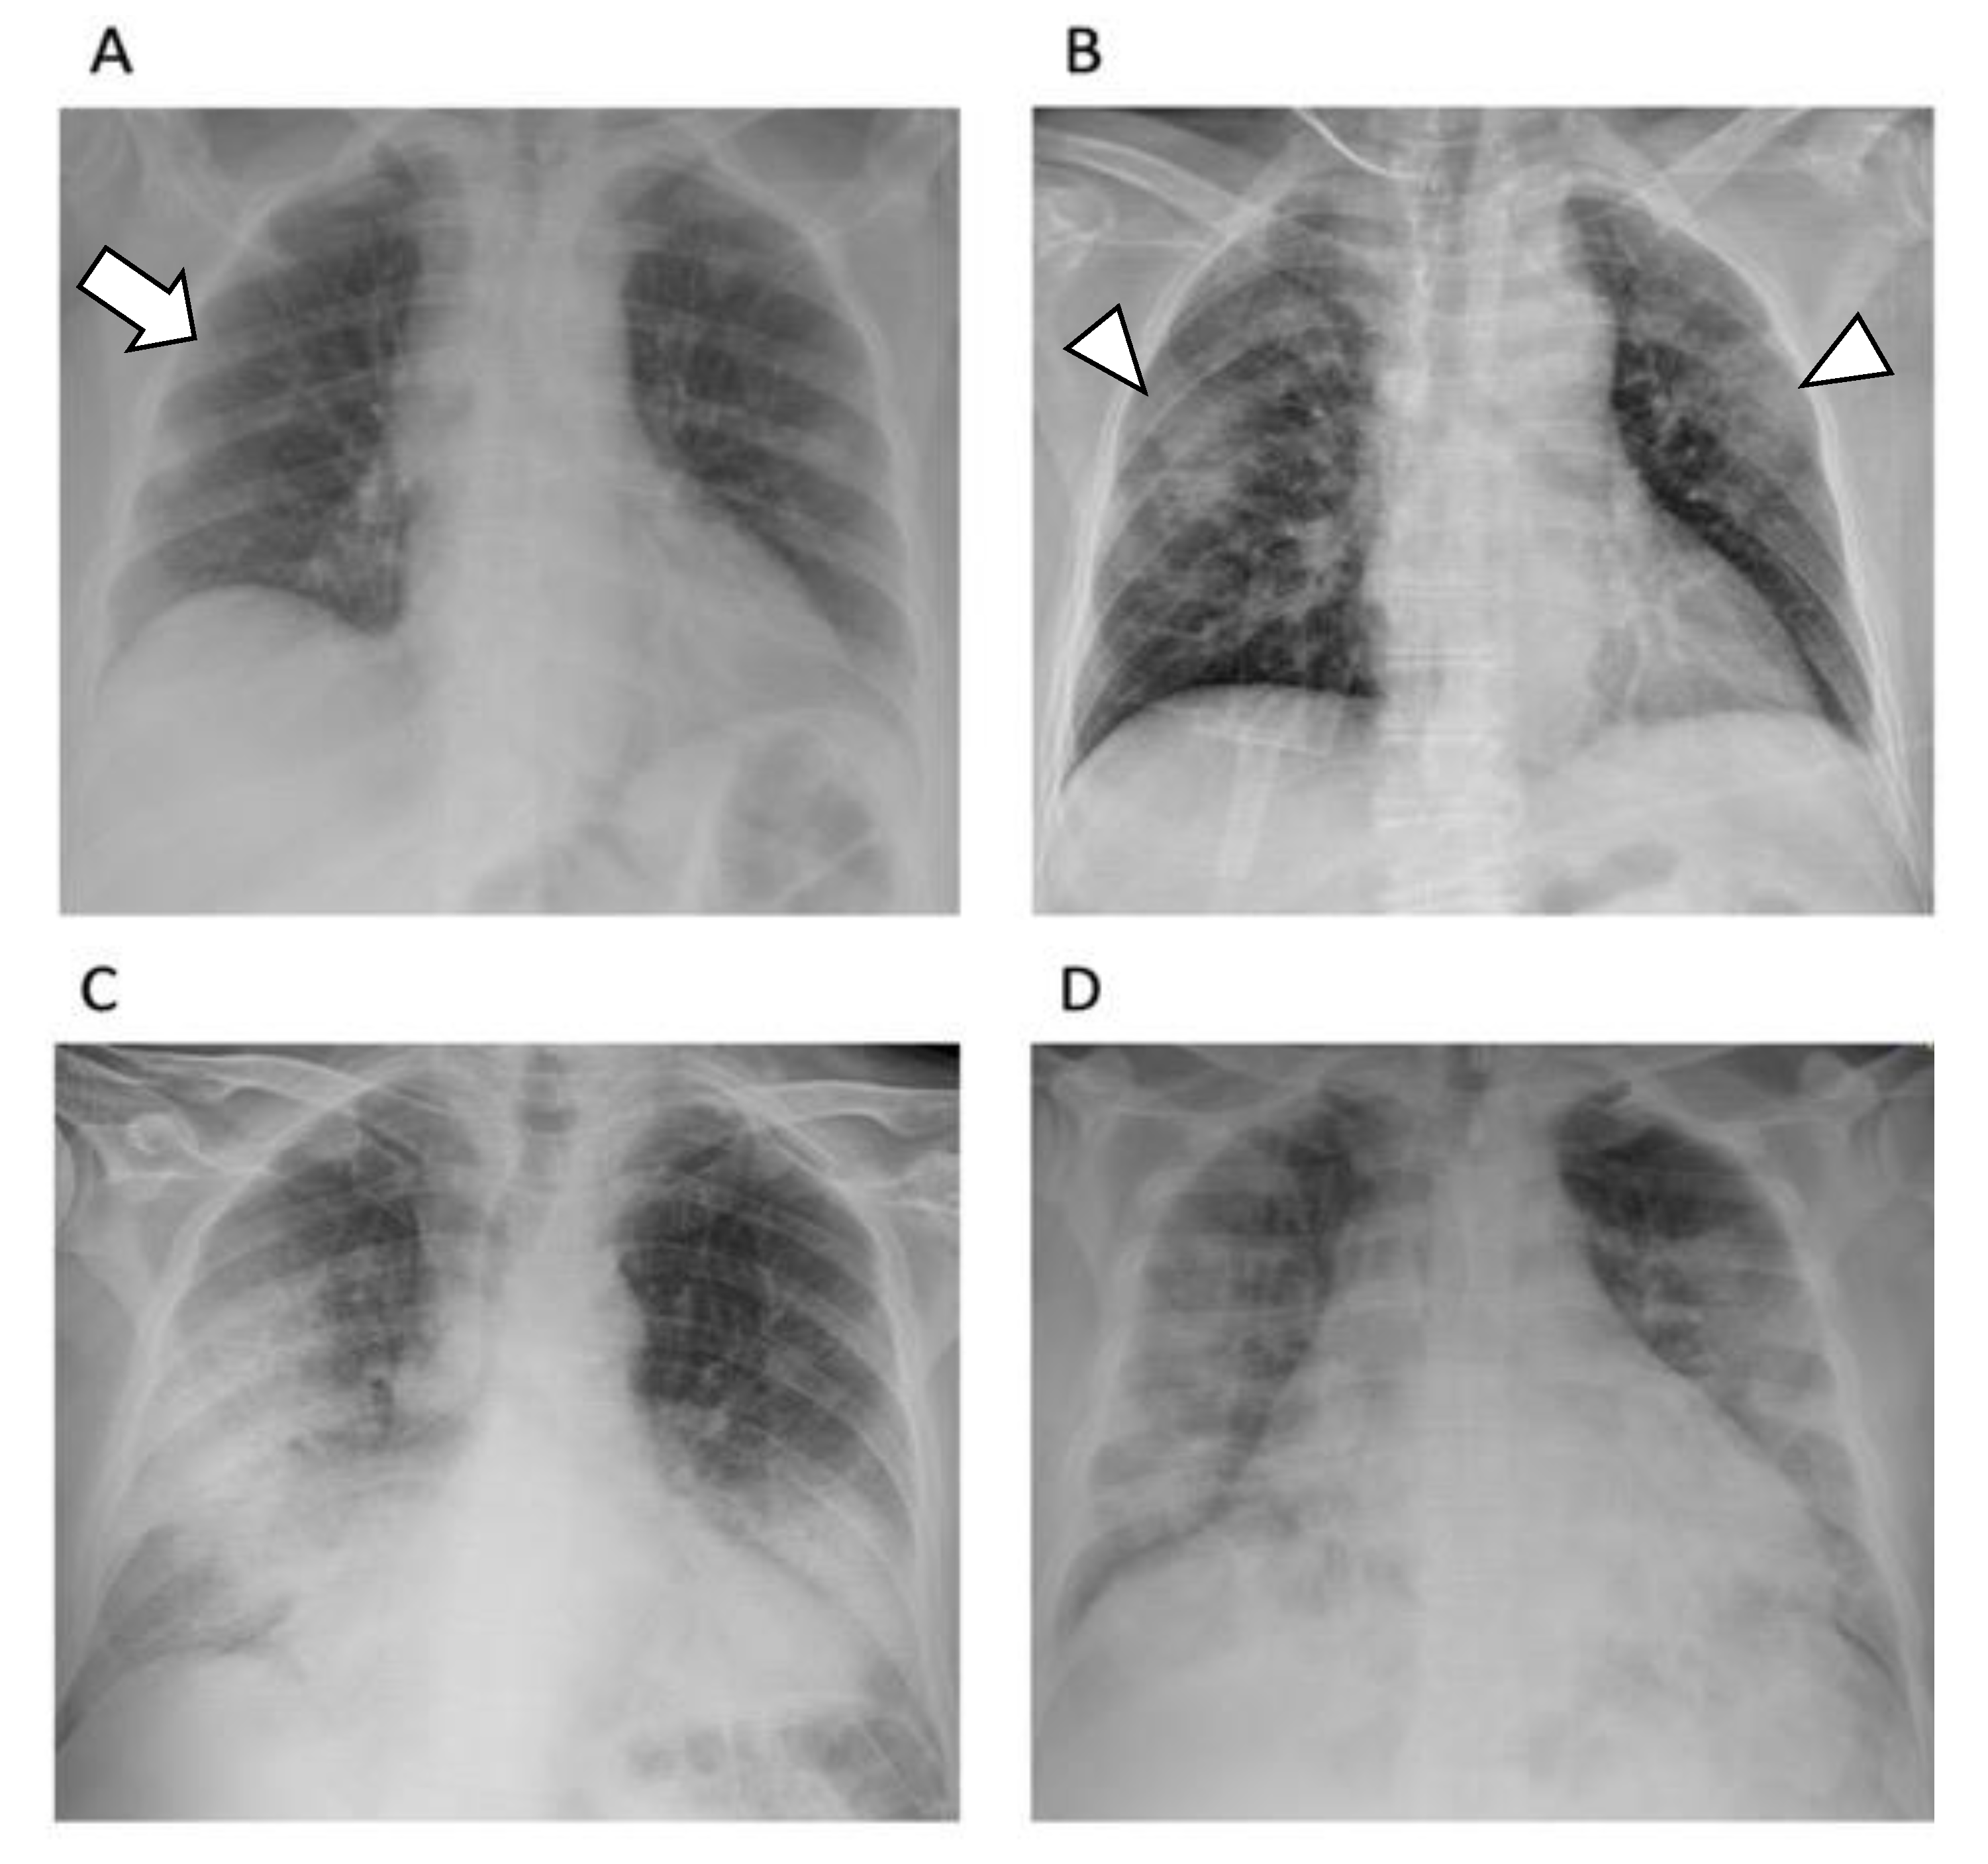

The CXR severity score is associated with the risk of intubation and hospitalization time [39]. Moreover, together with clinical data, CXR may help in predicting mortality and the need for ventilatory support [40]. Based on the American College of Radiology recommendations [41], CXR should be considered as a first diagnostic tool during pandemic peaks to obtain a quick, cheap, safe, and reproducible evaluation of lung involvement (Figure 3), although diagnostic accuracy is limited.

Figure 3.

Chest X-ray of patients affected by SARS-CoV-2 according to the extent of lung abnormalities involvement. (A). Lung involvement ≤ 25% (arrow). (B). Lung involvement 25–50% (arrowheads). (C). Lung involvement 50–75%. (D). Lung involvement ≥ 75%.